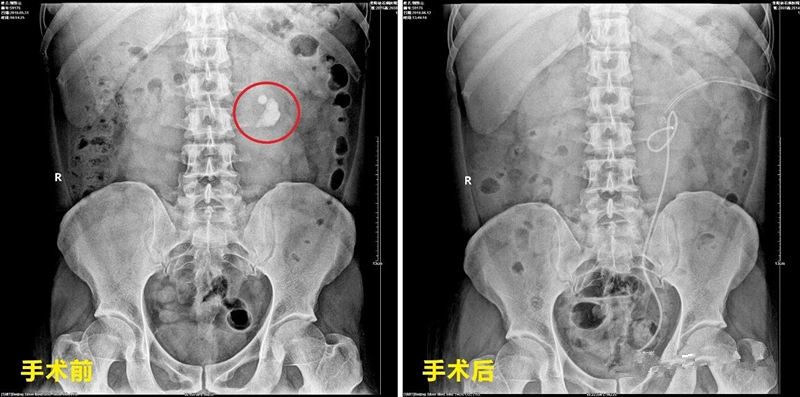

与正常人的肾脏相比,马蹄肾的位置比较深,并伴旋转畸形,所以穿刺比较困难 ,但是,医生凭借丰富的手术经验,在泌尿外科医护人员的认真配合下,娴熟开展“ 左侧经皮肾镜碎石取石术 ”,将患者肾盂内数枚3.0x2.5cm的淡黄色的结石顺利去除,手术过程中,患者生命体征平稳,第一期手术圆满完成。

短短几天之后,郭先生便可下床活动,7天后,恢复良好的他在医护人员的陪同下,再次进入手术室,迎来与肾下盏结石的最终“战役”。主治医生耗时35分钟,通过“ 左侧输尿管软镜钬激光碎石术 ”,将这枚1.2x1.0cm的黄色结石彻底粉碎。

▲郭先生术前术后X光对比图